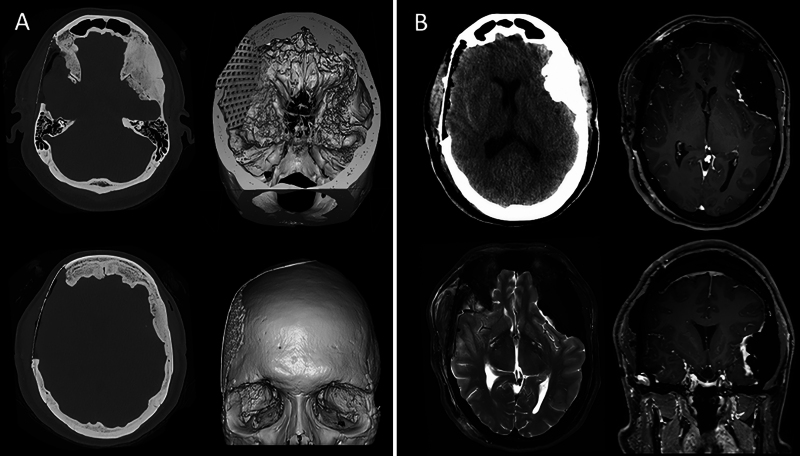

Observations: The authors present the case of a 52-year-old patient with progressive optic neuropathy due to bilateral hyperostotic frontotemporal MEP. Long-standing intracranial hypertension caused by mass effect had led to formation of a suprachiasmatic cyst deflecting the optic chiasm. The authors aimed to lower the intracranial pressure indirectly by performing a targeted, right-sided craniectomy with tumor removal and mesh cranioplasty. Postoperatively, reconstitution of brain anatomy and stabilization of the optic neuropathy were observed.